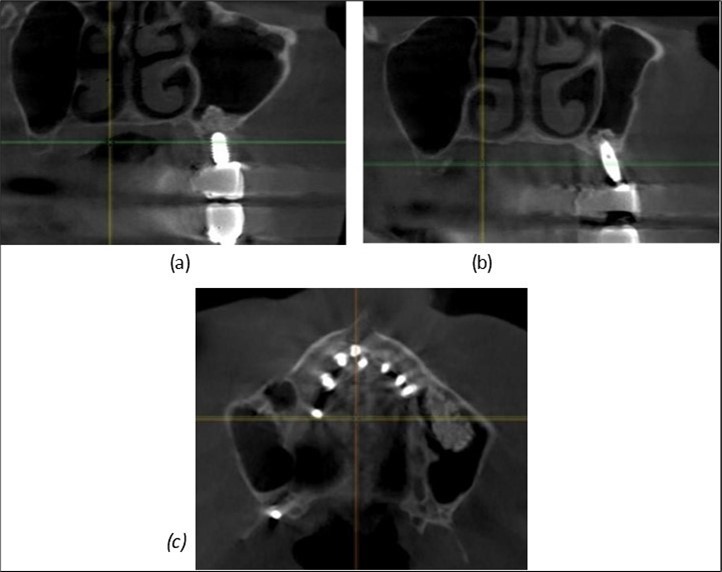

Figure 8.(a), (b) Sinus lift and grafting area with two stage implants before their removal. (c) area of fixation of BCS and TPG implants, avoiding the sinus lift and grafting area

Journal of Dentistry and Oral Implants - Periimplantitis

Figure 10.Implants in the palatal sinus cortical area to avoid bone grafting: (a) BCS implant partially fixed in the graft material mass, partially in the palatal cortex; (b) Implant fixed in the palatal cortex at the junction with the nasal cortex, behind the graft material mass.